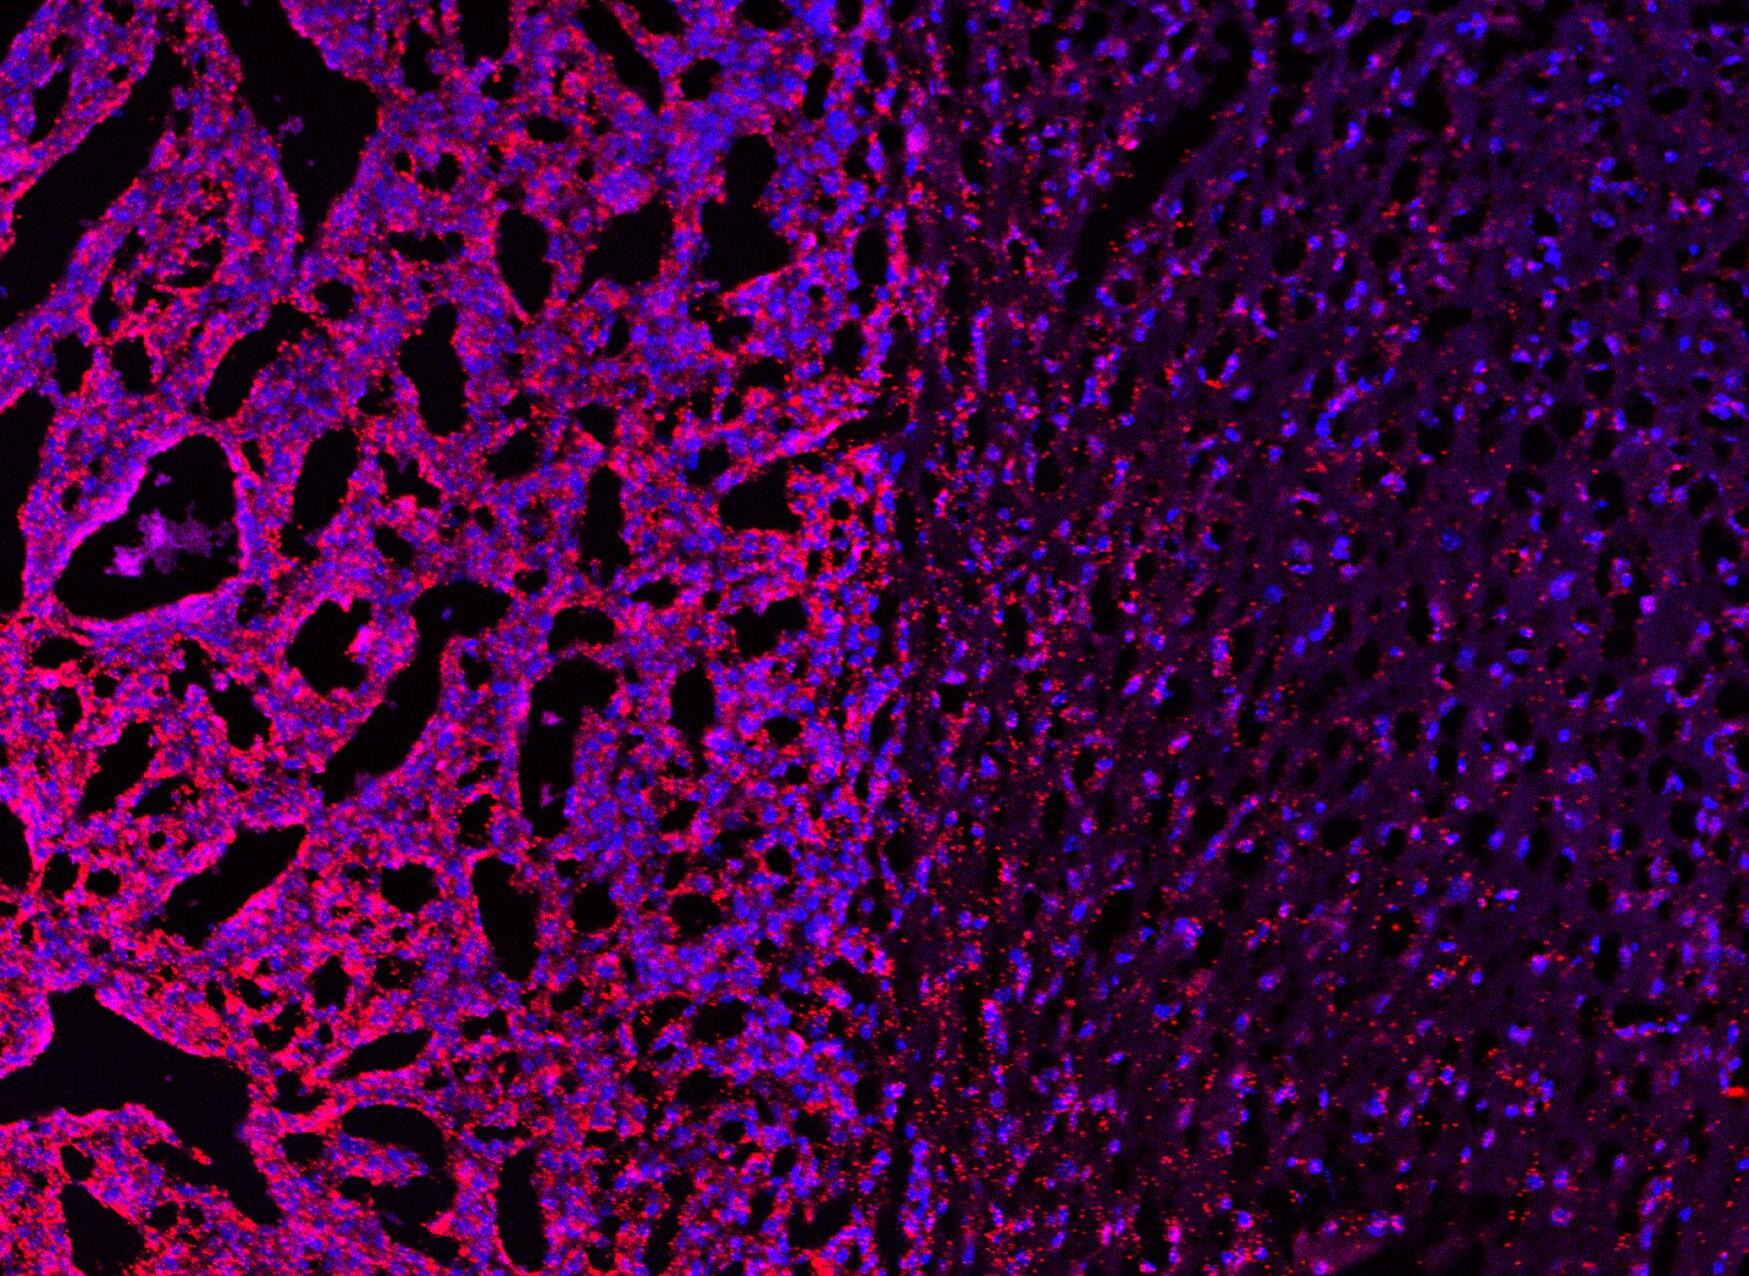

The team at the Brain Tumour Research Centre of Excellence at the University of Plymouth has published results of a game-changing project which could improve the success of future clinical trials for meningioma – the most common lowgrade brain tumour affecting adults.

Meningiomas are successfully treated by surgery and/or radiotherapy, but this can result in significant side effects and radiation damage to the brain. There are currently no approved chemotherapy options for meningioma patients which could spare them invasive surgery and radiation risks.

Now, researchers have discovered a new technique to grow meningioma tumour cells in the laboratory, providing an improved platform for drug discovery and testing which may increase the success of future clinical trials.

Professor Oliver Hanemann, Director of our Plymouth Research Centre, and his research team, have developed a new 3D meningioma cell culture model that more accurately depicts the cellular composition and 3D nature of meningioma tumours, and also mimics the same features demonstrated by invasive and treatment-resistant meningiomas. It’s exciting as this model provides a more robust drug-testing platform for this type of tumour.

Our Director of Research, Policy and Innovation, Dr Karen Noble, said: “This is a significant development in the hunt to find new and repurposed medicines to spare meningioma patients from undergoing surgery. For drugs to progress from preclinical testing into early phase clinical trials, researchers must first demonstrate that they work in laboratory models and are safe for healthy tissue. Employing this model for future drug development experiments will improve accuracy of preclinical test results, reduce failure rates of clinical trials, and ultimately improve patient outcomes.”

Prof Hanemann Meningioma cells